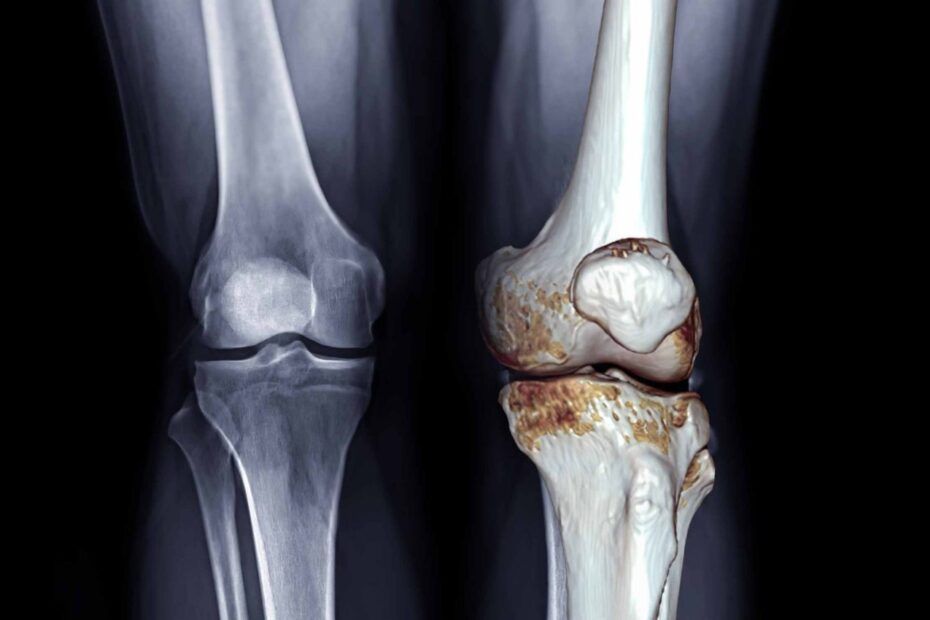

Artroza afectează peste 528 de milioane de persoane, iar aproximativ 365 de milioane suferă de forme localizate la genunchi, potrivit estimărilor globale. Boala duce la deteriorarea progresivă a cartilajului, rigiditate și limitarea mobilității, iar pentru mulți pacienți recomandarea standard rămâne administrarea de antiinflamatoare.

Scorurile privind durerea, rigiditatea și capacitatea funcțională au fost comparate, rezultatul fiind unul clar: metodele mecanice și fizice, care reduc încărcarea pe articulație și întăresc musculatura, oferă cele mai bune rezultate.

Ortezele semirigide sau rigide, numite și unloader braces, redistribuie forțele care trec prin genunchi și reduc presiunea asupra zonei deteriorate. Rezultatul: mai puțină durere la mers, capacitate mai mare de efort și reducerea inflamației locale.